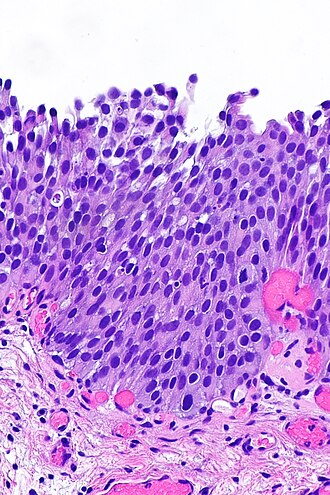

Urothelial dysplasia. H&E stain.

LM mild nuclear enlargement (~3x a resting lymphocyte) and hyperchromasia, mild disorganization of the architecture (some maturation), occasional mitotic figures - none atypical

• Mild nuclear enlargement (~3x a resting lymphocyte) and hyperchromasia.

• Slight disorganization of the architecture.

• Some maturation to the surface - important.

• Mitotic figures - occasional, none atypical.